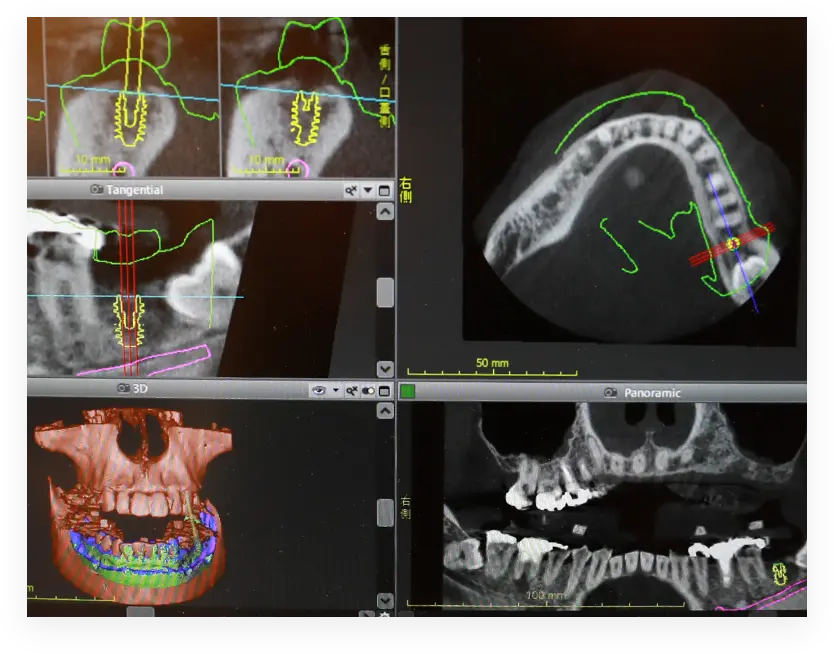

インプラント治療は外科手術を伴い、歯肉の切開や顎骨を削る工程があるため、血管や神経への影響を最小限に抑える安全性が求められます。当院では、患者様に安心して治療を受けていただけるよう「コンピューターガイドシステム」を採用し、歯科用CTで得た情報を基に、お口の3D画像を用いて精密な手術シミュレーションを行い、インプラントの位置や角度を事前に計画します。さらに、計画をもとに作製した「サージカルガイド(手術用テンプレート)」を使用することで、正確かつ安全にインプラントを埋め込むことが可能です。

インプラント治療を安全かつ確実に行うためには、詳細な術前診査が必要です。従来のレントゲン撮影では限界があるため、当院では歯科用CTによる精密検査を行っています。CT検査は、神経管や血管の位置、骨幅や骨質を正確に把握できるだけでなく、不要な骨移植や骨造成を避けるための重要な情報を提供します。また、当院の歯科用CTは高性能で鮮明な画像を撮影でき、より高度な診査・診断を可能にします。

これにより、患者様に最適な治療計画を立案し、治療の安全性と成功率を向上させています。